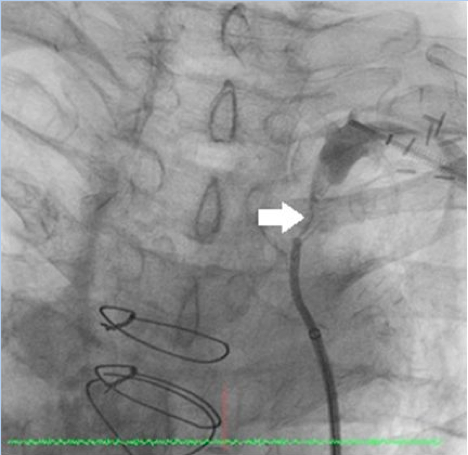

Figure 3. Right common carotid artery angiography: subclavian-carotid graft occlusion and surgical ligation of the right subclavian artery can be seen (click thumbnail to view larger image).

Upon transfer to our facility, a computed tomography angiogram (CTA) was performed, which revealed the bilaterally occluded bypass grafts and the ligated right SCA (Figure 2). Cardiac catheterization and angiography showed that both the proximal RCA and the left main were occluded. The SVG to RCA and OM1 were patent; SVG to D1 was occluded. The bilateral subclavian steals could be visualized with contrast injection into the bracheocephalic and left common carotid arteries (Figures 3 and 4). The LIMA was faintly visualized during the late filling phase of the left carotid angiogram (Figure 4); the left SCA and LIMA filled via collaterals from the left vertebral artery.